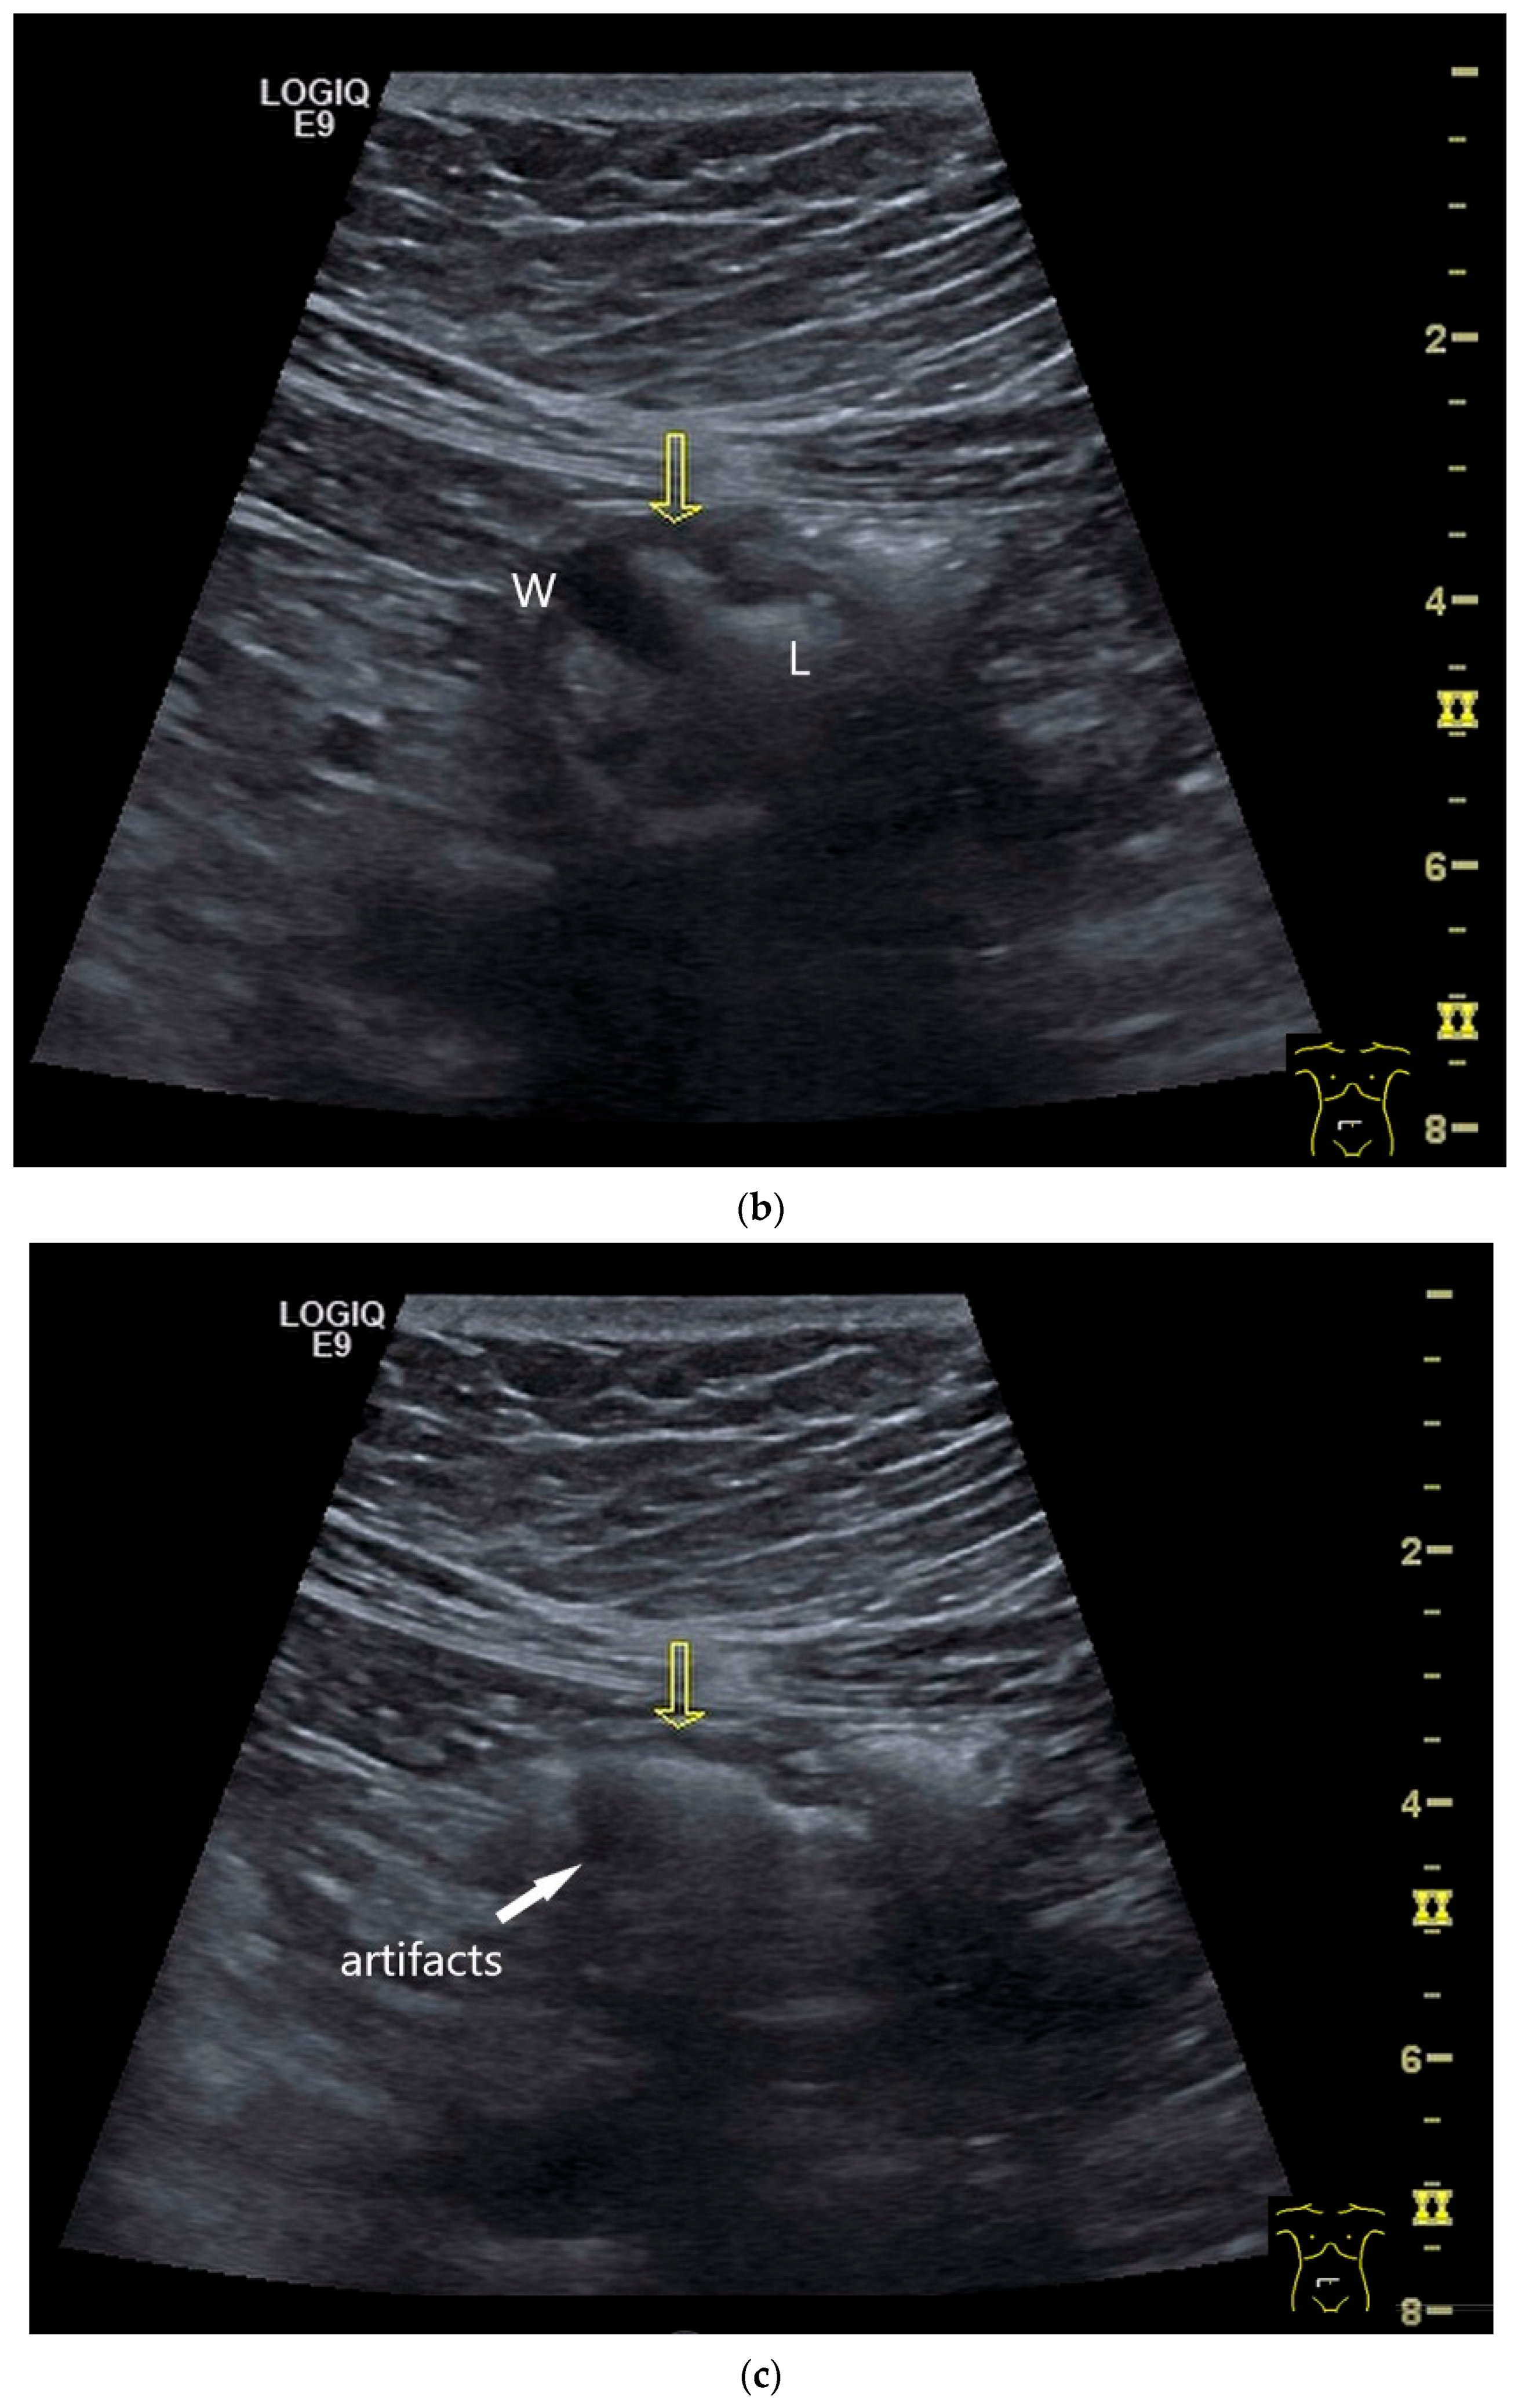

| GIST | Round hypoechoic masses, homogeneous or heterogeneous depending on size. They usually originate from the muscularis propria, which can be difficult to distinguish in US. Small vessels on CDI, hyperenhancement on CEUS. They move with the small intestine and can change position. |

| Gastrointestinal stromal tumor | Approximately 30% in the small intestine, 50–70% in the stomach. | Round, hypoechoic lesions with reference to the lamina muscularis propria. |